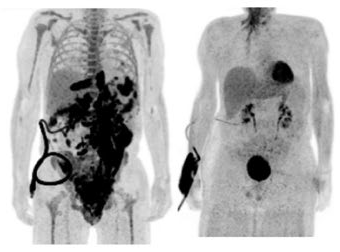

Chimeric Antigen Receptor T-cell (CAR-T) therapy is a revolutionary approach cancer treatment. T cells extracting a chimeric antigen receptor (CAR) that targets specific cancer cells can destroy cancer cells while sparing healthy cells. CAR-T was successfully used to treat certain aggressive blood cancers. Within 28 days of the CAR-T cell therapy, 50 percent of patients responded positively and around 80% to 90% of patients will go into remission after six months (Terry Fry, 2024, Massimo Martino et al, Front. Immunol., 02 May 2024). With the recent progress in automated CAR-T cell manufacturing facility the preparation of cells to be infused back into a patient can be ready within 14 days.

Six FDA-approved CAR T cell treatments are available, including the pioneering CRISPR-based clinical trials for treating sickle cell disease and beta-thalassemia.

Photo Medical College of Wisconsin, Oct 5th, 2020